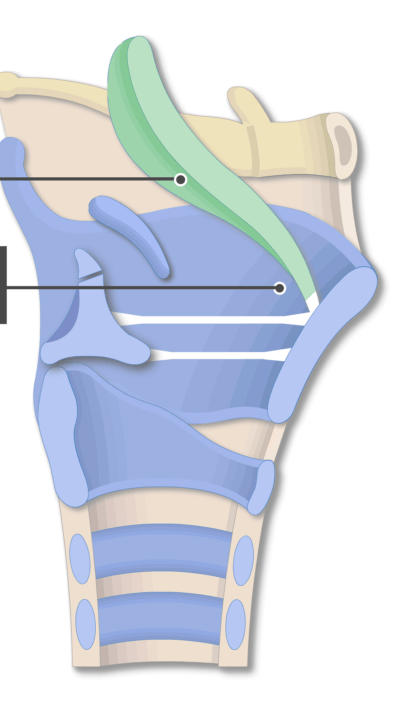

Name #3

Epiglottis (epiglottic cartilage)

Name the bottom structure

Thyroid cartilage

Name the structure

Laryngeal prominence

Name the blue structure

Arytenoid cartilages

Name the yellow structure

Cricoid cartilage

Cricothyroid joint